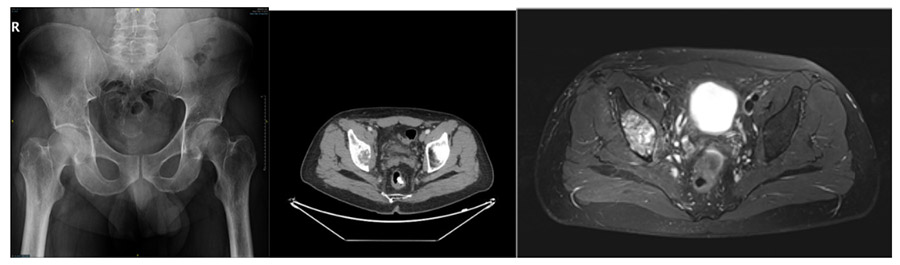

CASE 20: Bladder cancer increases the risk of fracture in the right hip (acetabulum) due to metastasis.

Before the surgery: X-ray shows a metastatic focus in the right acetabulum, and MRI and CT scans show damage.